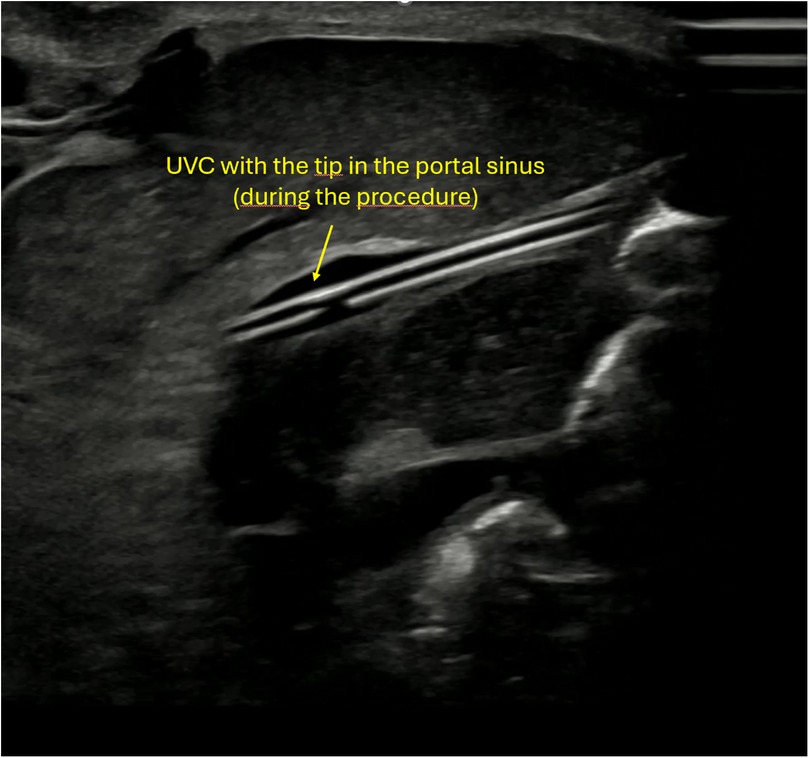

Figure 3

Ultrasound image showing the tip of an umbilical venous catheter (UVC) positioned in the portal sinus during the procedure.

Figure 3. Ultrasound image showing the umbilical venous catheter (UVC) during the procedure, positioned just before entry into the ductus venosus.